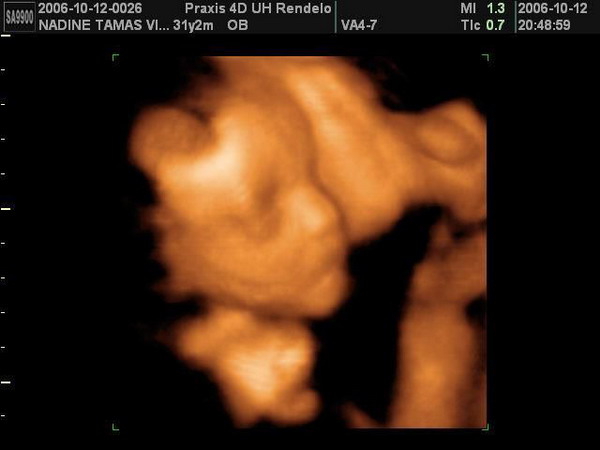

Úgy néz ki, hogy nekünk is két puncisunk lesz, minden eddigivel ellentétben a csütörtöki 4D ezt mutatta. :lol:

Köszi, de elég meggyőző volt a 4D, mert tutira punikat

lehetett látni. :lol:

A 12.heti Uh-n fütyit véltünk látni, de úgy tűnik, hogy nem jól láttuk mi azt, vagy lehet, hogy az elmúlt 13 hétben felszívódott :lol:

Párom fogta is a fejét rendesen mikor mondta az UH-s néni "és ott van a másik kislány"